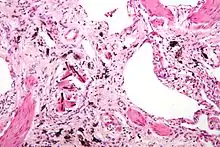

Micrograph of asbestosis showing the characteristic ferruginous bodies and marked interstitial fibrosis (or scarring). H&E stain.